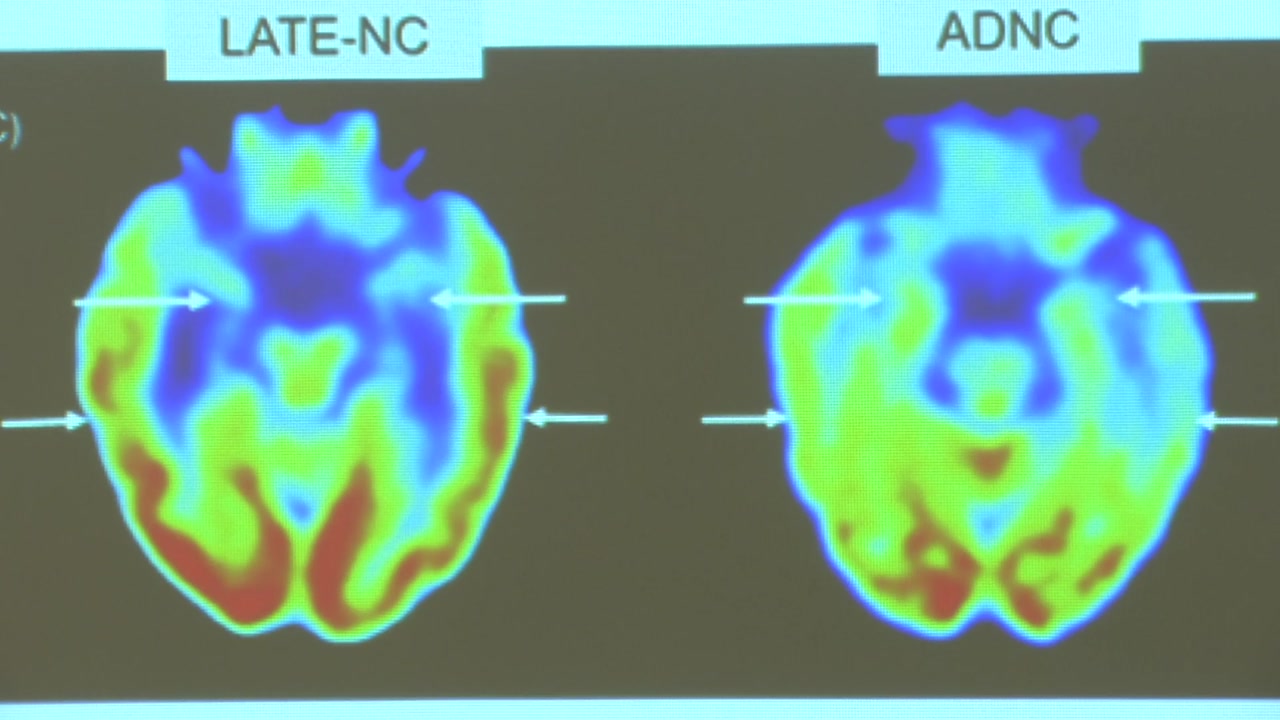

[문소영 / 아주대학교 의과대학 교수 : 알츠하이머병, 파킨슨병, LATE(80대 이후 치매) 이런 것과는 조금 다르게 뭉뚱그려져서 전두엽과 측두엽이 망가지면 어떤 치매 증상이 나타나는지를 연구하고 있습니다.]